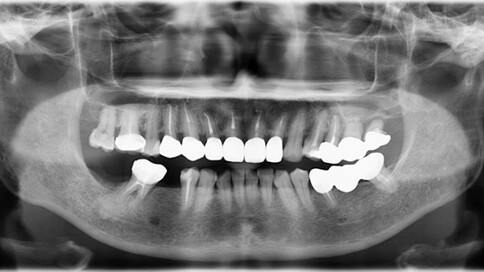

面對前牙(門牙)的缺損或美觀問題,我們通常會根據「修復範圍」與「牙齒健康狀況」,在全瓷冠與陶瓷貼片之間做選擇。

✨ 三、 四至六顆:微笑曲線重塑

Case 7:外突內收打造理想笑線,提亮色階。

Case 8:拆除舊連排假牙,換成獨立顆數全瓷冠。